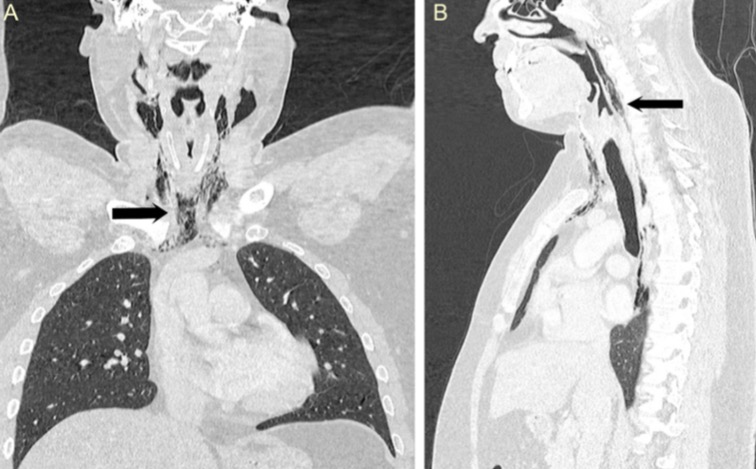

НемедицинаFigure 2. (А и Б) Фронтальная и сагиттальная компьютерная томография шеи и грудной клетки, показывающая эмфизему в области шеи и пневмомедиастинум, простирающуюся от основания черепа до позвонка T9 (черная стрелка).